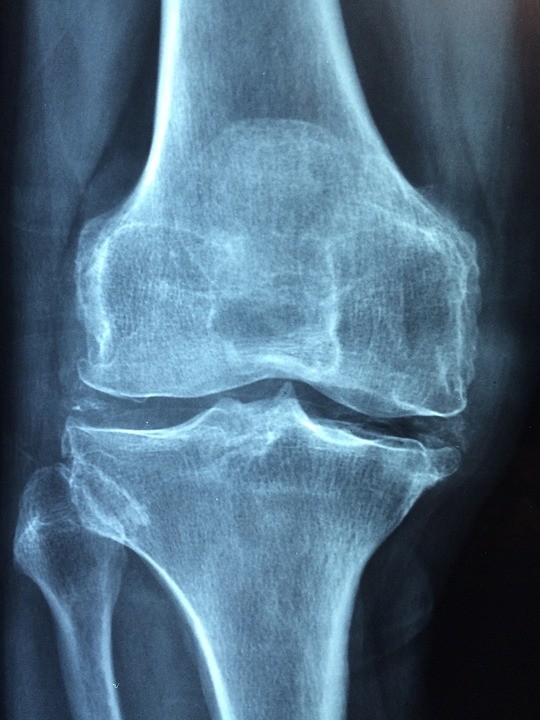

한편 파열된 연골판이 제대로 관리되지 않아 뼈의 연골을 건드려 닳게 만드는 상황에 이르면, 무릎의 통증과 운동제한은 더욱 심각해진다. 심지어 무릎을 수동으로 굴곡, 이완 시키면 뼈가 갈리는 사각사각 소리도 들을 수 있다.

이러한 분들이 찾는 것이 바로 무릎주사이다. 보통 연골주사, 뼈주사, 자가혈주사 등 세 가지로 구분되어 홍보가 되고 있다.

이름도 매력적인 연골주사의 정식명칭은 관절 내 하이알루론산 주사이다. 끈적끈적한 활액을 관절강에 주입하여, 관절의 윤활작용을 돕는 것이다. 그러나 이는 치료가 아닌 증상완화요법이며, 효과가 짧고 주사과정에서 외부세균의 감염위험이 뒤따른다.

뼈주사는 스테로이드 주사이다. 통증과 부종을 빠른 시간에 잡아준다. 그러나 스테로이드의 부작용이 워낙 커 연골변성, 무혈성괴사, 지방괴사, 피부변성, 의인성 쿠싱 증후군 등의 위험이 뒤따른다. 이 또한 마찬가지로 외부세균의 감염위험도 높다.